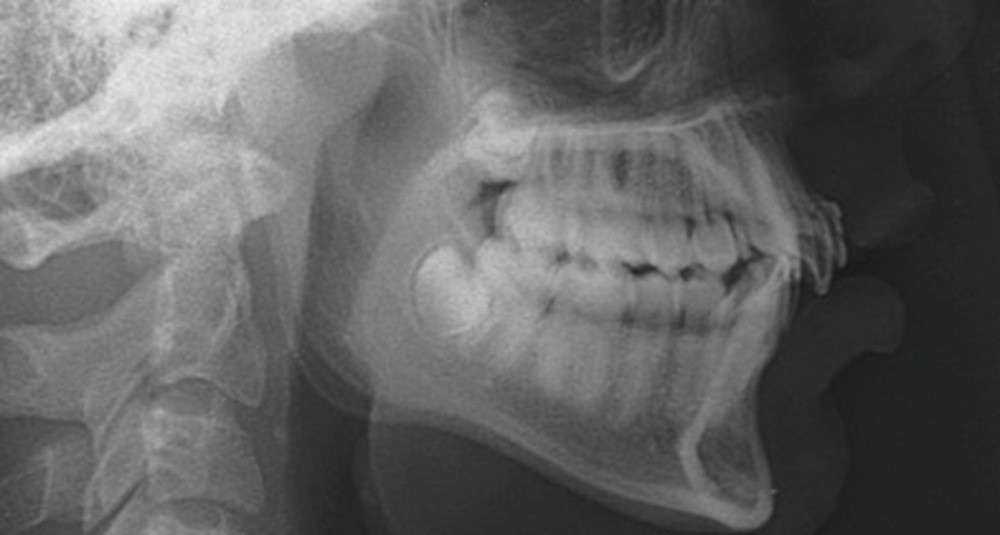

Son incisive centrale supérieure droite (11) présente un défaut de structure amélaire sévère, compromettant une technique restaurative pérenne a minima. L’examen de la panoramique (fig. 1e) et de la radiographie rétroalvéolaire de 11 (fig. 1f) objective une fracture coronaire verticale, ainsi qu’une racine grêle et courbe, peut-être en rapport avec un ancien traumatisme [1]. Le rapport couronne clinique/racine clinique est défavorable.

L’analyse de la téléradiographie de profil (fig. 1g) confirme une classe II squelettique à tendance hyperdivergente avec une normo-position de l’incisive mandibulaire dans sa symphyse. L’âge du patient et la croissance mandibulaire en rotation postérieure (travaux de Björk) ne permettront sans doute pas une correction de la classe II squelettique sans version de l’incisive mandibulaire.